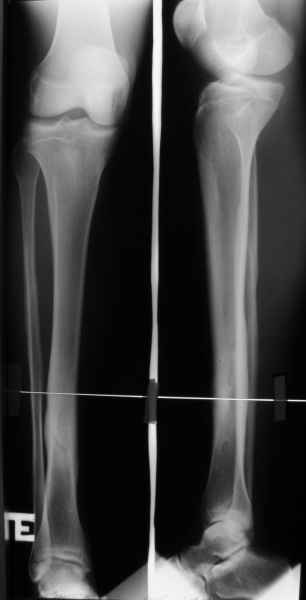

остеосинтеза (кроме детей, разумеется). На прошлой неделе оперировали 11-летнюю девочку с низким переломом обеих костей голени. Гвоздик не поставить и пластинка вроде как перекрывает зону роста. Аппарат пришелся как нельзя кстати.

Ведь у каждого случалось лечить пациентов с переломами месячной и более давности. Так вот одномоментно выправить "ось-длину-ротацию" уместно как раз постепенно. Затем забить гвоздь и все. Ваш аппарат, видимо, будет обладать всеми необходимыми для этого